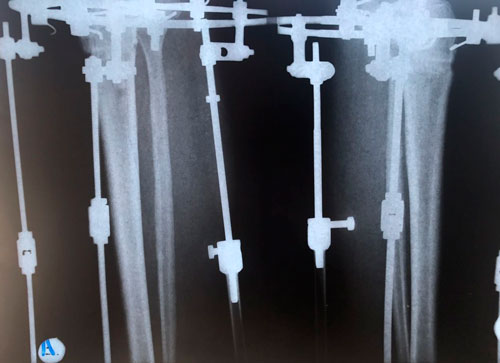

Дата операции 21.03.2018г.

Дата снятия аппаратов 06.07.2018г.

Срок лечения 105 дней.